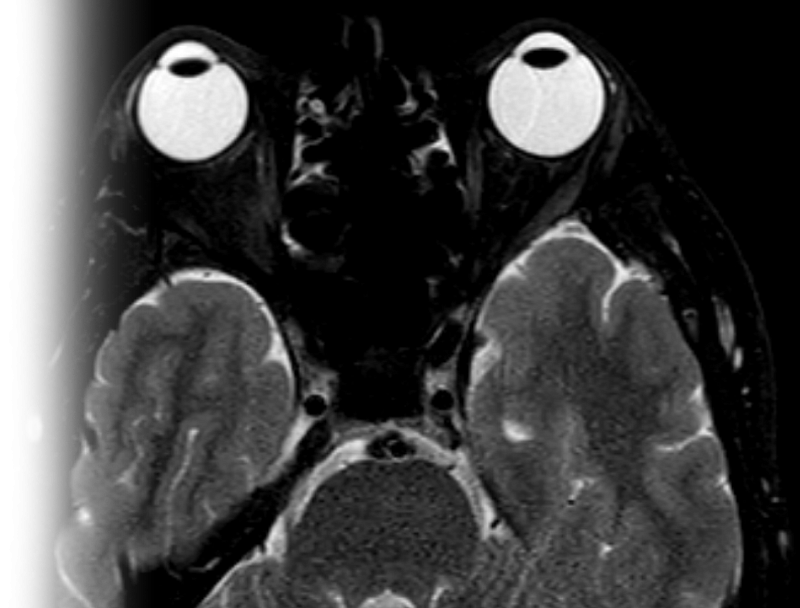

Магнитно-резонансная томография орбит – важный метод исследования, который позволяет оценить структуры орбит.